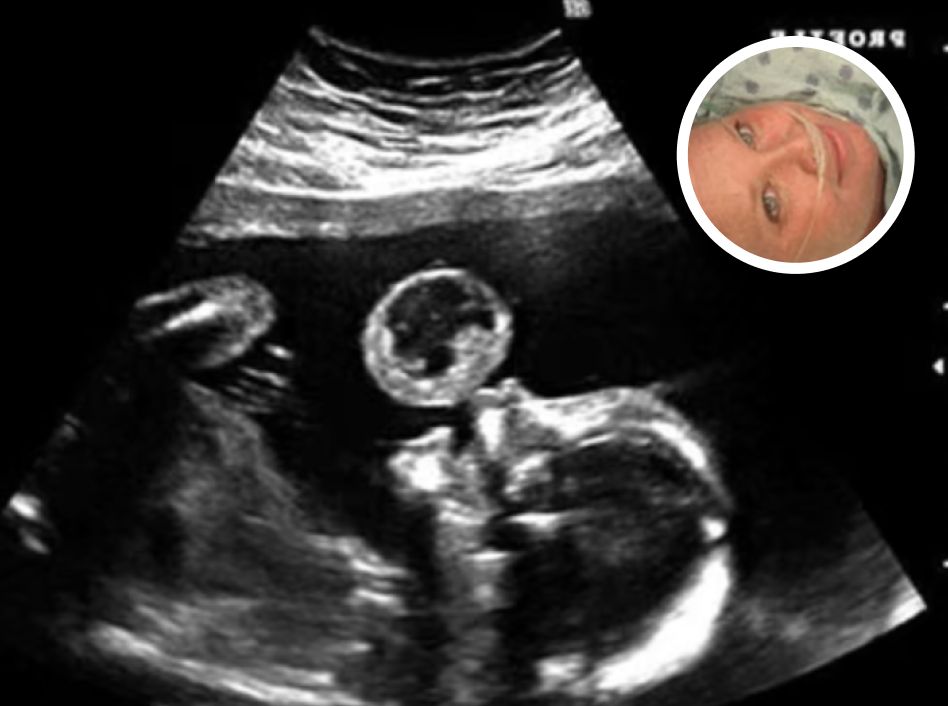

Tammy Gonzalez, a Miami resident, was expecting her baby when she went in for a standard ultrasound—a moment many mothers anticipate with joy, as they catch the first glimpse of their child. But during this appointment, doctors noticed something alarming. Hovering just above the baby’s mouth was what appeared to be a large, translucent bubble.

After further analysis, the bubble was diagnosed as a teratoma—a rare and often life-threatening tumor that can develop in utero. These tumors are seen in approximately 1 in every 100,000 births and can grow rapidly, threatening the baby’s ability to survive. The news was devastating. Doctors warned Gonzalez of the risks: not only could the tumor lead to miscarriage, but continuing the pregnancy could also endanger her own health. The medical recommendation was clear—termination.

The procedure was led by Dr. Ruben Quintero, director of the Fetal Therapy Center at Jackson Memorial Hospital in Miami, who agreed to attempt the groundbreaking surgery. Using a quarter-inch incision, he threaded a small endoscopic camera and precise surgical instruments through Gonzalez’s abdomen and into the amniotic sac, allowing him to visualize the tumor in real time.

With the camera showing a close-up of the tumor, Dr. Quintero made a critical decision. Using tiny tools, he severed the tumor’s stem. The moment the tumor detached, it floated away from the baby’s face, its danger neutralized.

Because the tumor was too large to remove safely through the incision, it was left inside the womb, floating in the amniotic fluid. Over the next four months, as Gonzalez carried her daughter to term, the tumor continued to shrinknaturally.